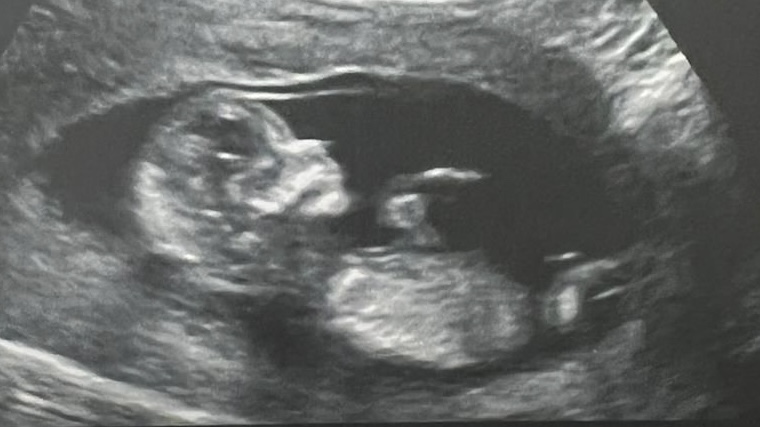

3. Ultrasound Picture Announcement – this is the simple and most quick way to announce. I shared the ultrasound picture of the baby with very close friends without captioning. They called back in 30 seconds to check if it was true!!